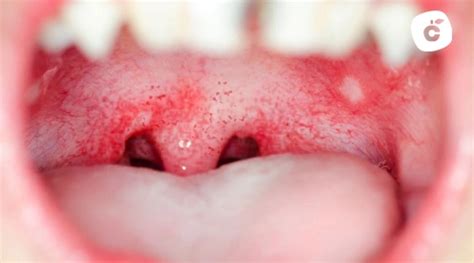

Las manchas rojas en el paladar son alteraciones en el color de la mucosa que pueden surgir por diversas razones. Estas manchas pueden presentar variaciones en su forma y tamaño, así como en los síntomas que pueden acompañarlas. La identificación correcta de estas manifestaciones es vital, ya que pueden ser indicativas de diferentes condiciones de salud. Es fundamental prestar atención a su aparición y características, ya que el diagnóstico temprano puede ser vital para descartar afecciones serias.

Las manchas rojas en el paladar se diferencian por varias patologías o síntomas, ya que existen diversos tipos. Son diferentes los tipos de manchas en el paladar y se distinguen según los síntomas y patologías:

- Las aftas son lesiones con tamaño que pueden variar desde muy pequeñas a más grandes y que se manifiestan con una mancha que tiene un núcleo de color claro alrededor de un halo rojo. Se pueden manifestar en boca, lengua, mejillas, labios, encía, garganta o paladar.

- El virus del herpes suele ser un virus que, una vez contagiado, no se va de nuestro organismo. Los pacientes que sufren de herpes suelen ser afectados por esto varias veces al año, sobre todo en períodos de estrés. La manifestación oral del herpes es un conjunto de vesículas que pueden manifestarse en el paladar.

- Esta patología está causada por un hongo que se manifiesta con manchas rojas o manchas blancas en el interior de la cavidad oral. Muchas veces está presente en pacientes diabéticos, en mujeres que sufren de cándida a nivel genital, en portadores de prótesis y también en niños pequeños.

- Los virus coxsackie son responsables de patologías a nivel de manos, pies y boca, en particular en el paladar. La manifestación de este virus suele cursar con ampollas y manchas rojas que, a nivel oral, se manifiestan sobre todo en la zona del paladar.

- En algunos casos, las manchas rojas en el paladar o a nivel oral pueden indicar que hay algo que no está funcionando correctamente en el organismo, por lo que será importante una intervención temprana.